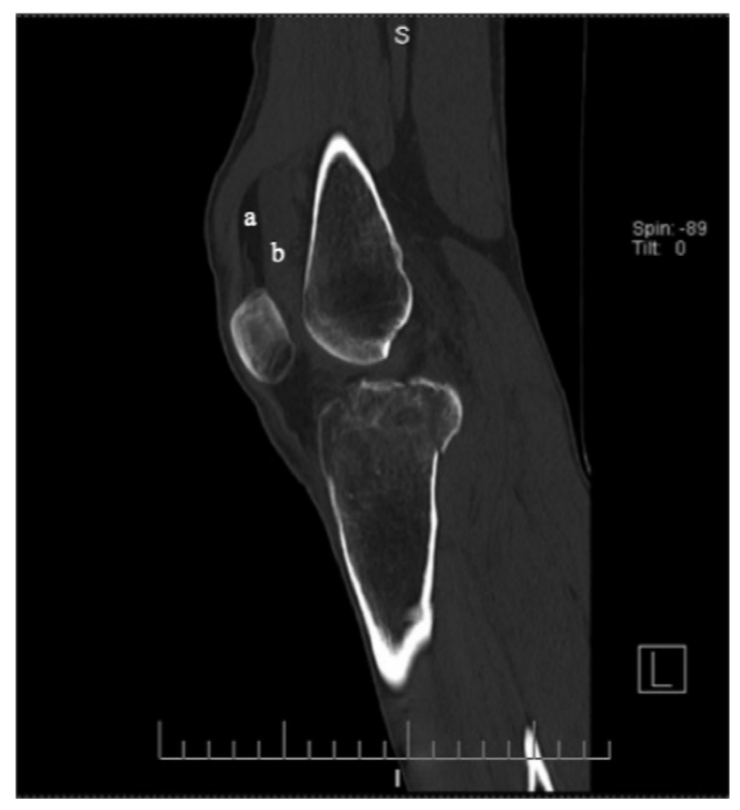

③ 肘关节

肘关节积脂血症与肘关节脂肪垫征原理类似,在肘关节骨折后关节腔内积血将肘关节脂肪垫抬高,高度提示桡骨小头骨折。

病例7 一例10岁患者肘关节外伤,侧位可见明显关节积脂血症。